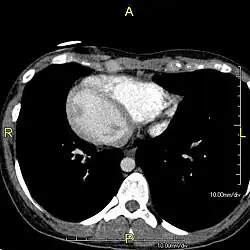

Diagnosis of situs inversus can be made using imaging techniques such as x-ray, ultrasound, CT scan, and magnetic resonance imaging (MRI).[9]

The condition affects all major structures within the thorax and abdomen. Generally, the organs are simply transposed through the sagittal plane. The heart is located on the right side of the thorax, the stomach and spleen on the right side of the abdomen and the liver and gall bladder on the left side. The heart's normal right atrium occurs on the left, and the left atrium is on the right. The lung anatomy is reversed and the left lung has three lobes while the right lung has two lobes. The intestines and other internal structures are also reversed from the normal, and the blood vessels, nerves, and lymphatics are also transposed.

If the heart is swapped to the right side of the thorax, it is known as "situs inversus with dextrocardia" or "situs inversus totalis". If the heart remains on the normal left side of the thorax, a much rarer condition (1 in 2,000,000 of the general population), it is known as "situs inversus with levocardia" or "situs inversus incompletus".

Situs inversus is found in about 0.01% of the population, or about 1 person in 10,000. In the most common situation, situs inversus totalis, it involves complete transposition (right to left reversal) of all of the viscera. The heart is not in its usual position in the left chest, but is on the right, a condition known as dextrocardia (lit. 'right-hearted'). Because the relationship between the organs is not changed, most people with situs inversus have no associated medical symptoms or complications.[1]